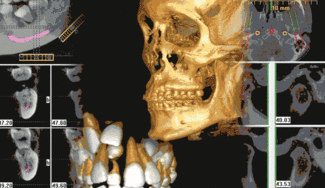

Once the scan is complete, the 3-D imaging software takes over. These 3-D images precisely replicate the positions, shapes, and measurements of every scanned facial structure, including the maxilla, mandible, TMJ, sinuses, nasal cavity, and area back to the cervical spine. Within the software, these views can be sliced and rotated for diagnostics and treatment planning. It’s like picking up a cup and looking at it from all sides instead of looking at a picture of it, and then slicing the cup any way you want to see and measure its internal structure.

Specialized procedures are particularly aided by 3-D technology. Defining the position of vital structures can help avoid complications during implant planning and placement, as well as third molar removal. For those dentists placing implants, the “nerve marking estimation tool” locates previously undetected nerve canals. The precise slices of the mandible and maxilla assist in determining implant type, size, and location.

Orthodontists can accurately pinpoint root positions, impacted teeth, supernumerary teeth, and other conditions that affect tooth movement. Clinicians who treat TMJ disorders benefit from viewing the TMJ areas from all angles. The list goes on.